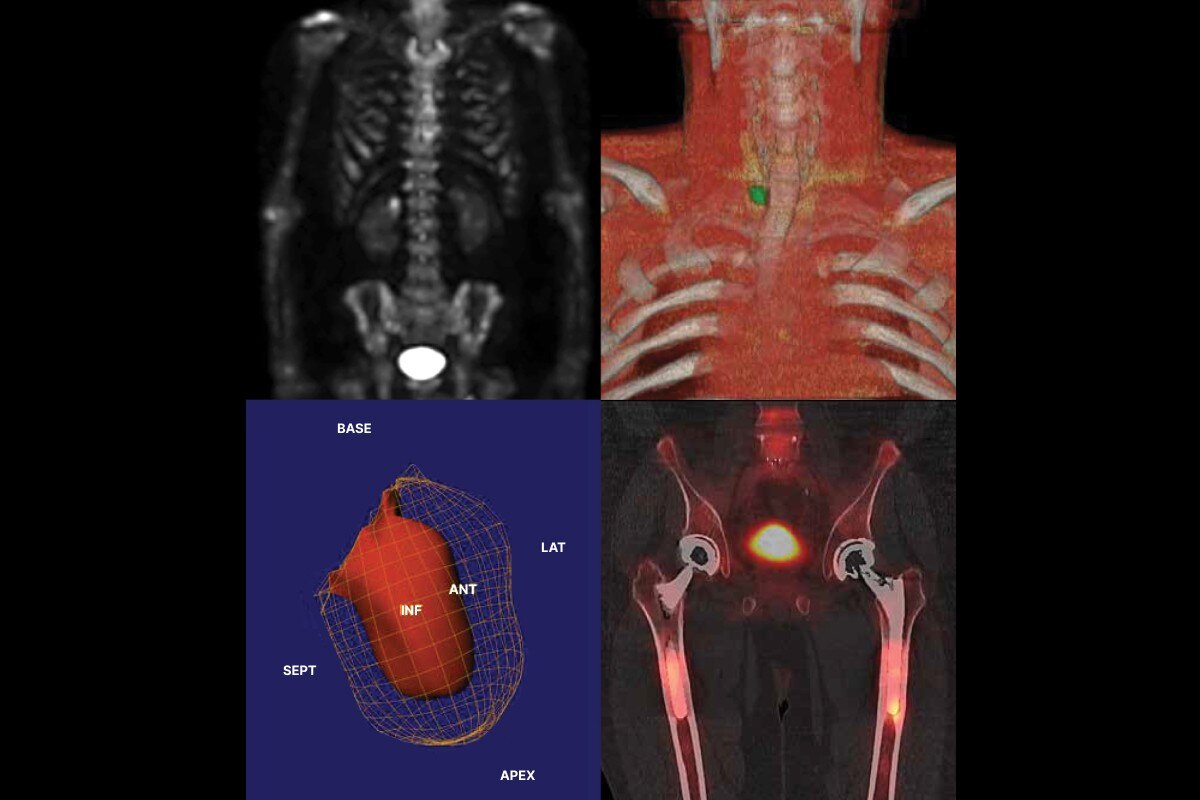

Un arceau 3D qui s'adapte à votre routine: de l'arthrodèse à la fracture, en passant par l'angiographie et le placement de stents

L'arceau OEC 3D permet de passer rapidemment et facilement d'une imagerie 3D à une imagerie 2D et vice versa. Cette polyvalence permet de bénéficier de l'imagerie 3D pour un large champ d'applications cliniques, de la chirurgie du rachis à la traumatologie en passant par la cardiologie et la chirurgie vasculaire. Enfin un arceau 3D adapté à tous les blocs opératoires.

L'OEC 3D tire partie de la technologie de reconstruction AW de GE HealthCare, permettant de tirer le maximum de l'imagerie 3D. Vous pouvez analyser les images et les volumes grâce aux outils du Volume Viewer, incluant le mode multi-oblique, la navigation à travers les 512 coupes, le fenêtrage ou le zoom.